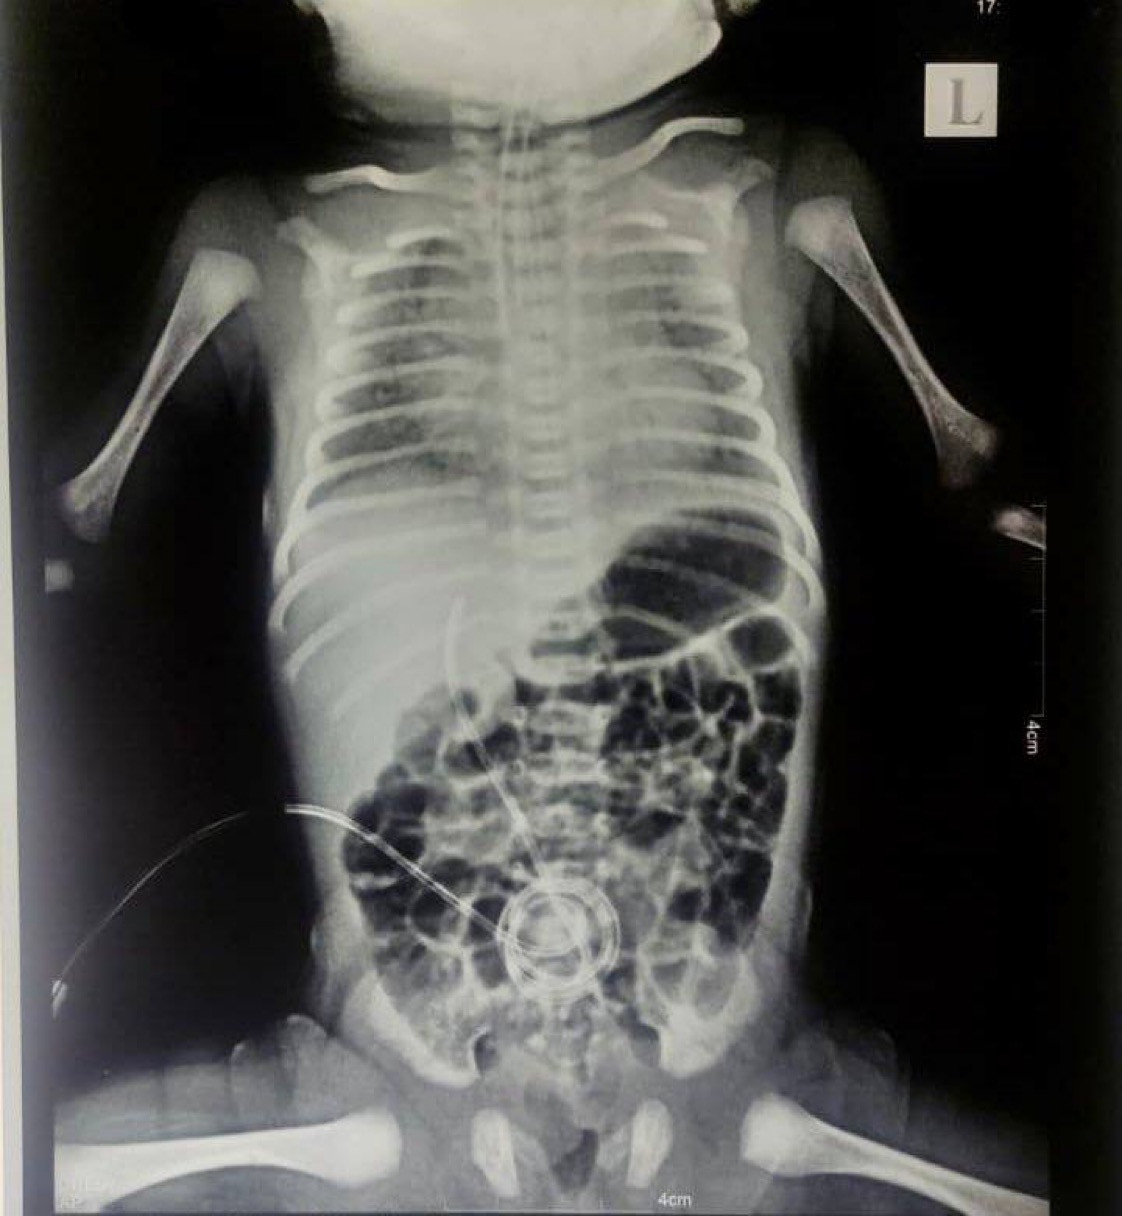

"WHITE LUNG SYNDROME" IS A COVID19 "VACCINE" ADVERSE REACTION: "Fully Vaccinated Mother’s Dying Newborn With White Lungs. A pattern of Multisystem Inflamma